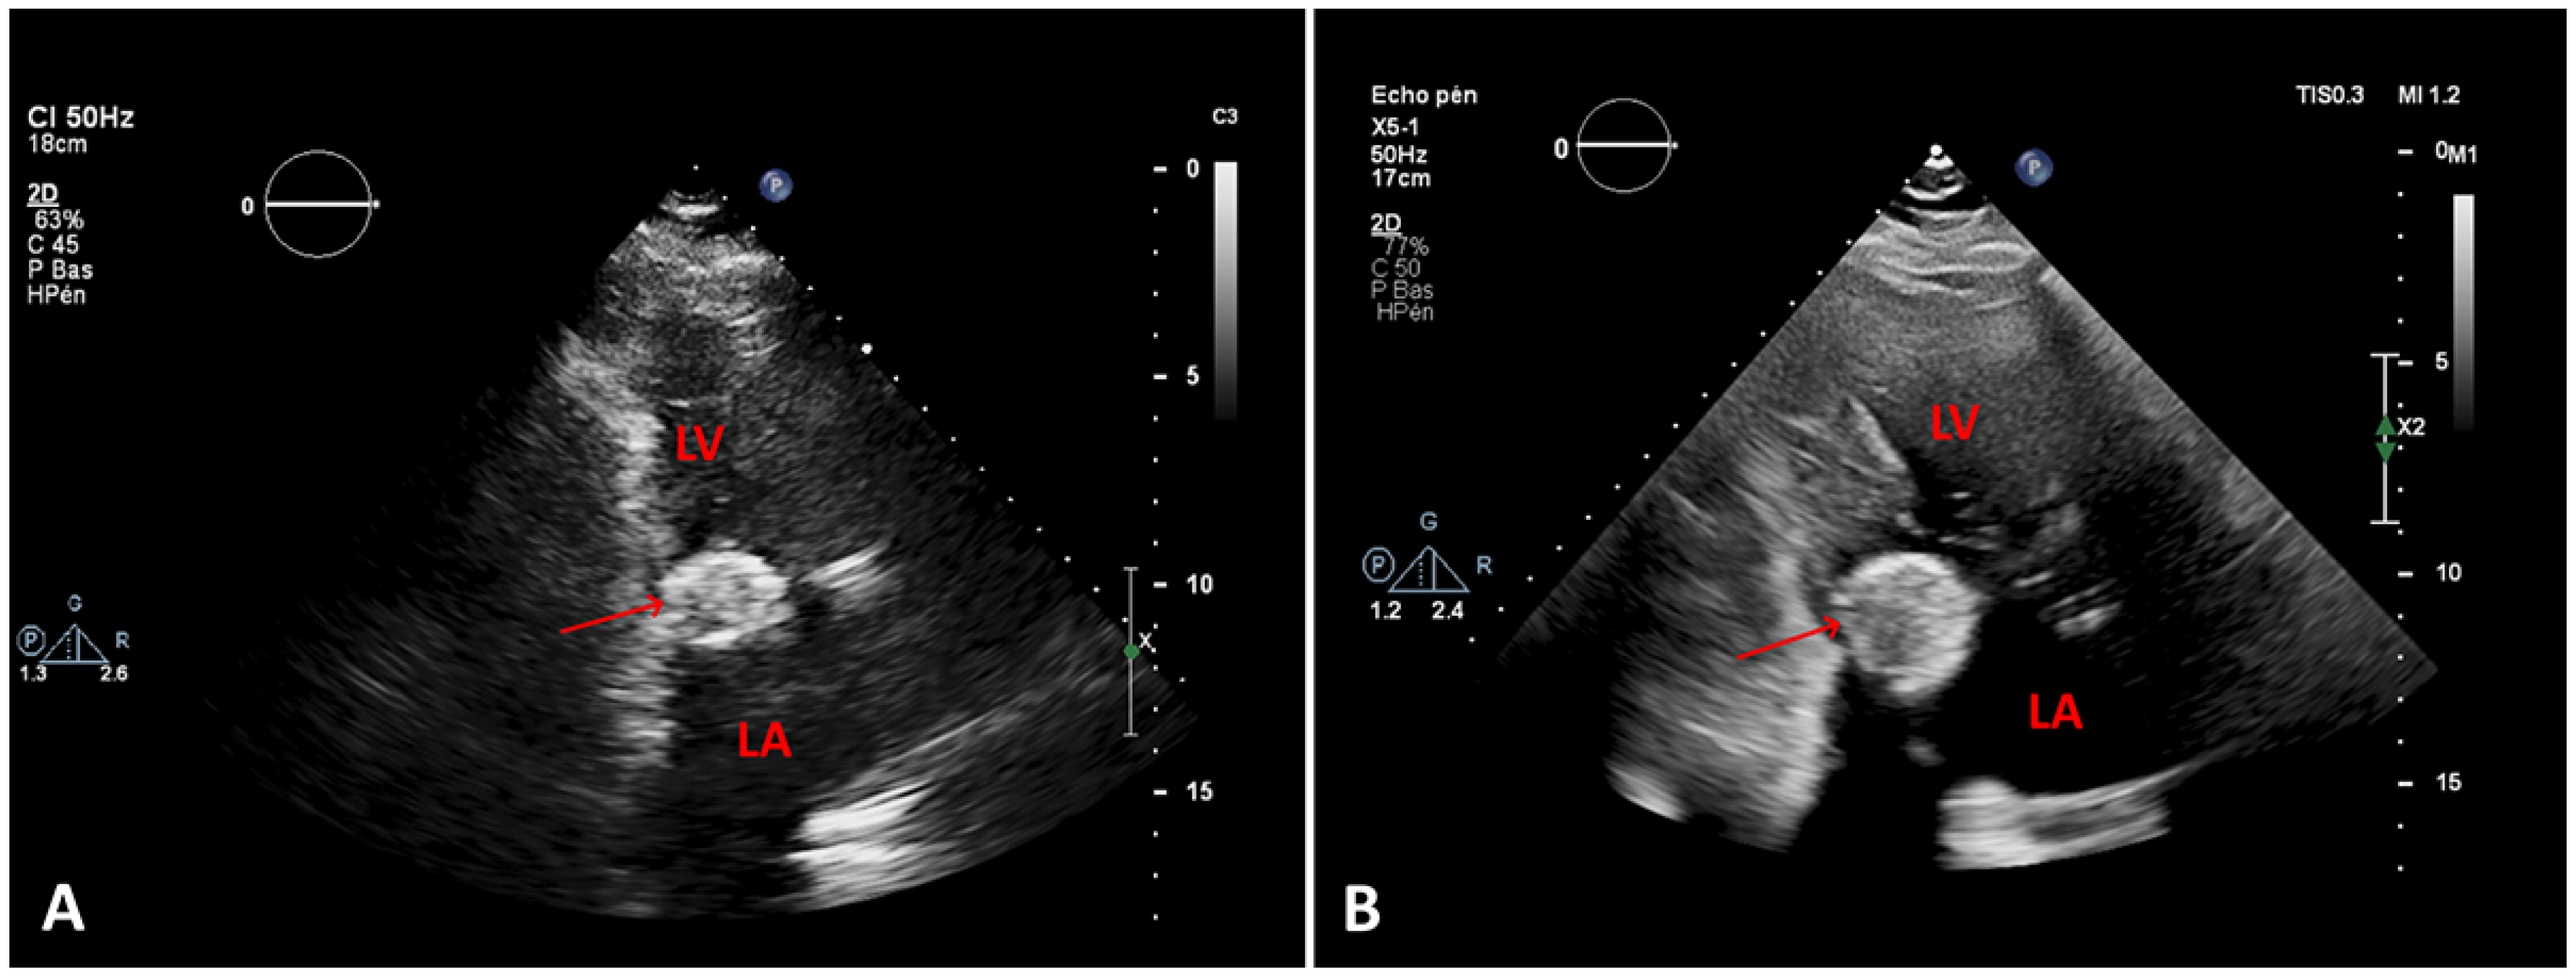

Figure 2. A. First transthoracic echocardiogram (TTE), two-chamber view, at the time of diagnosis B. TTE 4 years later, showing the increasing size of the caseous calcification of the mitral annulus (arrows). LV: left ventricle; LA: left atrium

In the emergency department the patient’s vital signs (oxygen saturation 88%), clinical examination (tachypnoea, orthopnoea, bilateral lung crackles), laboratory tests (elevated N-terminal pro-B-type natriuretic peptide [NT-proBNP]) and chest X-ray (lung congestion) confirmed the diagnosis of acute heart failure, albeit of unclear aetiology: her blood pressure was only mildly increased, mild troponin elevation argued against an acute coronary syndrome, haemoglobin levels and heart rate were stable (Table 1). The patient was admitted for oxygen supplementation and intravenous diuretics with rapid recovery ensuing in a few days. A TTE documented normal heart function but an increase in the size of the cardiac mass ( 46 mm × 31 mm compared with 36 mm × 27 mm 4 years before), the mean gradient across the mitral valve was unchanged at 6–7 mm Hg at a heart rate of 65 bpm (Figure 2) The mitral valve area obtained by two-dimensional planimetry from the parasternal short axis view was 1.2 cm2 (Figure 3B). No other significant valve disease was found. Transoesophageal echocardiography (TOE) showed moderate mitral stenosis. The mitral valve orifice measured by three-dimensional planimetry was 1.4 cm2 (Figure 3A). Remarkably, there was an increase in the mean diastolic mitral gradient from 6 mm Hg at the time of the TTE to 13 mm Hg on TOE, probably due to a higher heart rate of 85 bpm (Figure 5). A CT scan showed an increased size of the mass (Figure 4). Due to the frailty of the patient and in accordance with her wish not to undergo any invasive treatment, surgery was not proposed. The patient was discharged before being admitted 2 months later for another episode of acute heart failure treated with intravenous diuretics. The therapeutic attitude was altered and at this time the patient was again discharged for ambulatory follow up for treatment adjustment and only symptomatic management if acute heart failure happens again.